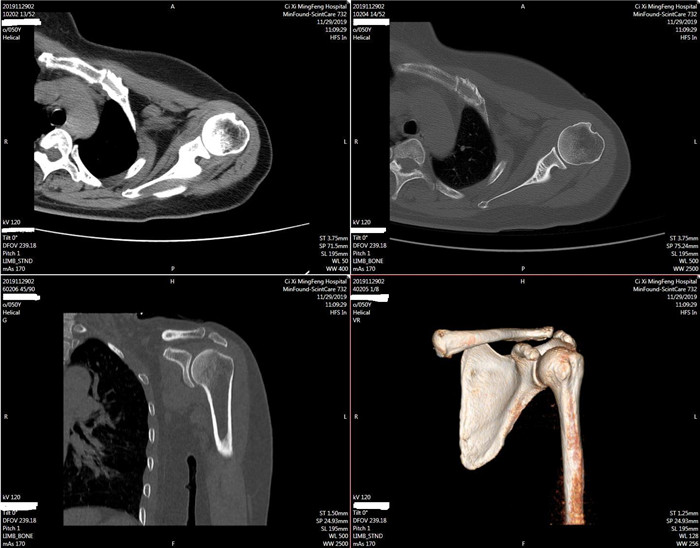

明峰CT搭載了領(lǐng)先的硬件技術(shù)平臺及系統(tǒng),強(qiáng)大的掃描能力可滿足臨床的各種要求,呈現(xiàn)更極致的細(xì)節(jié),為各臨床科室提供高品質(zhì)的圖像。薄層掃描,消除部分容積效應(yīng),提高各向同性。配合高分辨率算法,有助于細(xì)微結(jié)構(gòu)和形態(tài)學(xué)顯示。